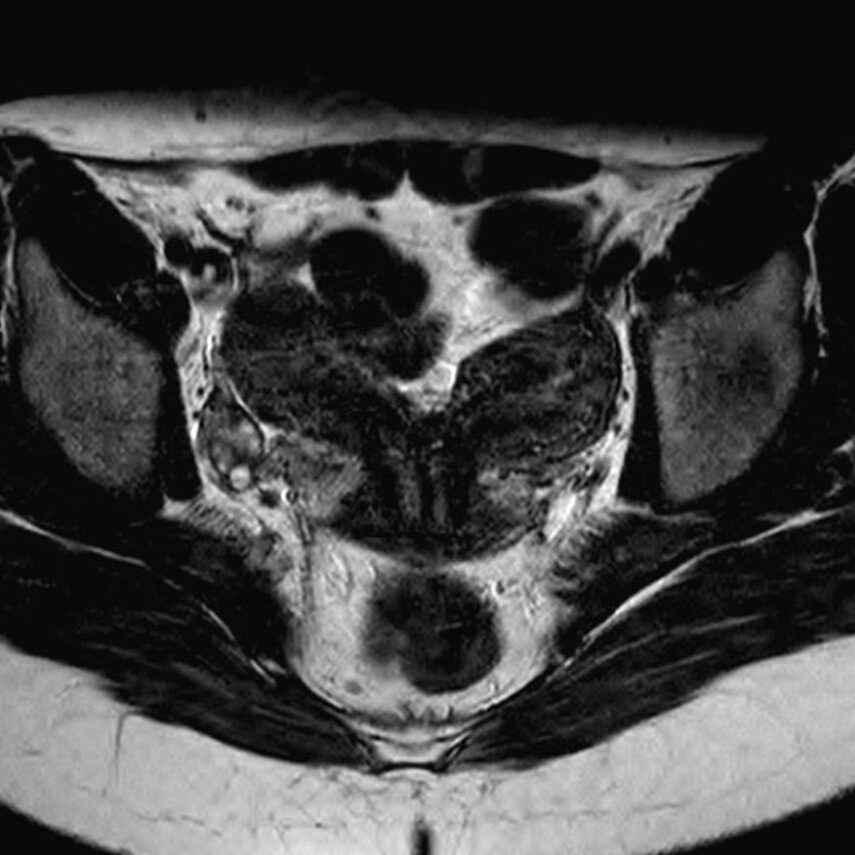

El diagnóstico del útero didelfo se realiza mediante la realización de exámenes de imagen como ultrasonidos, resonancia magnética o histerosalpingografía. Estos estudios permiten visualizar la estructura interna del útero y determinar si hay dos cavidades separadas o una división central, así como la presencia de dos cuellos uterinos.